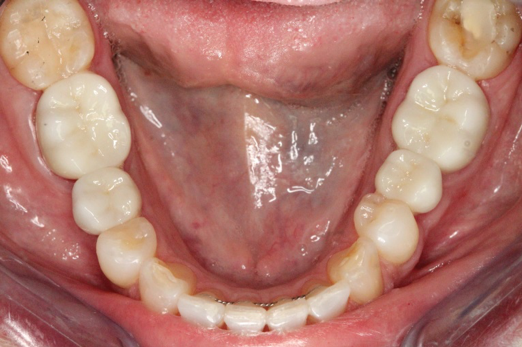

Fig 7. 12 weeks postoperatively.

Figure 7

Figure 3 through Figure 5 show the fitting of a one-piece multiple splint using a light-cured acrylic, along with flowable composite to adhere the splint to the three ceramic dental implants. The splint was to remain out of occlusion, without any occlusal forces for the 12-week osseointegration period. The patient was instructed to chew on the other side of her mouth for the 12 weeks before returning to the dental practice for simple removal of the splint. Removal of the splint revealed optimum results. The soft tissues were pink, with keratinized gingival margins completely surrounding the ceramic implants and consistent with what most dentists observe with the periodontium around periodontally healthy natural teeth (Figure 6 and Figure 7).